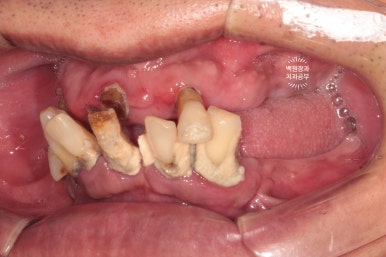

교합면에서 촬영한 사진입니다.

치아를 다 발치해야겠다는 생각이 절로 드는 환경이셨어요.

혹시나 보이시나 모르겠지만, 상당히 잇몸뼈가 얇음이.. 예상되는 상태였습니다.